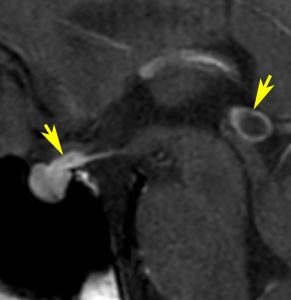

この例は18歳,HCG 0.1mIU/ml,尿崩症で発症しました。神経下垂体ジャーミノーマなので,下垂体前葉のみが残って後葉から視床下部が腫瘍化しています。よくよく見ると松果体にもごく小さな腫瘍があります。右のCISS画像で松果体の腫瘍化が明瞭です。

経鼻生検術で下垂体後葉部分がgerminomaということを確認してからICE (IFO/CDDP/VP-16)を1コース加えて3週間後の画像です。腫瘍は灰白隆起の部分を残してほぼ消失しています。松果体部の腫瘍も消えています。典型的なgerminomaの化学療法反応性を示しています。下垂体前葉機能は正常,尿崩症も少し良くなりました。

軽度の複視のみで発症した20代前半男性です。右上のように松果体腫瘍の前に割れ目が入るように第3脳室があり,両側視床に浸潤するために軽度の視床浮腫があり,ガドリニウムで強く増強され一部にのう胞があります。これだけでもgeriminomaにかなり特有の所見です。さらに,灰白隆起(矢印)のところに小さな神経下垂体germinoma腫瘍があります (bifocal tumor)。HCGは測定限界以下,AFP 2.5で,水頭症はありません。全ての臨床所見がgerminomaであることを示しています。

生検病理診断をしないでICE化学療法を1コース終えた後の画像です。腫瘍は消失しています。これでgerminomaであることが確認できたので,ICE化学療法を2コース追加して,25.2グレイの全脳室照射をして治療を終了しました。